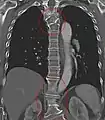

Block vertebrae occur when there is improper segmentation of the vertebrae, leading to parts of or the entire vertebrae being fused. The adjacent vertebrae fuse through their intervertebral discs and also through other intervertebral joints so that it can lead to blocking or stretching of the exiting nerve roots from that segment. It may lead to certain neurological problems depending on the severity of the block. It can increase stress on the inferior and the superior intervertebral joints. It can lead to an abnormal angle in the spine, there are certain syndromes associated with block vertebrae; for example, Klippel–Feil syndrome. The sacrum is a normal block vertebra.